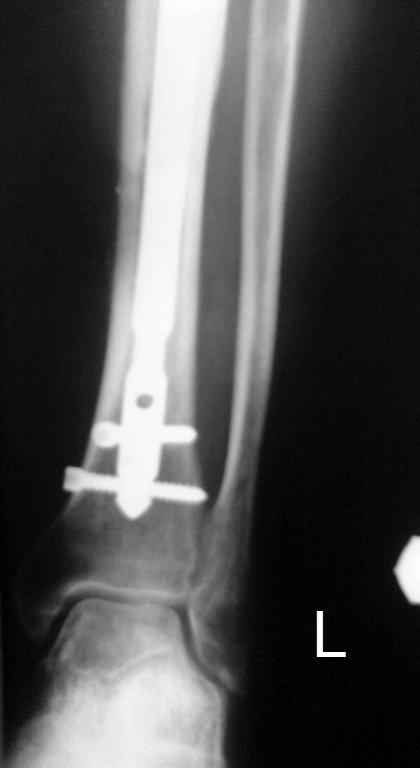

Тогда можно рассмотреть вопрос одновременного удаления штифта, мышечной (в данной области применим проксимально отсеченный лоскут камбаловидной мышцы) или микрохирургической (что более надежно) пластики дефекта мягких тканей, остеотомии проксимального фрагмента большеберцовой кости, остеосинтеза блокируемым штифтом с а/б покрытием, наложения простого аппарата Илизарова (можно из полуколец) для дистракции на штифте. При данном варианте пациент сохраняет возможность полной опоры на ногу, что очень важно для заживления у пожилого пациента) и отпадает необходимость в проведении дополнительный операций (при благоприятном развитии событий).

Выкладываю картинки похожей пациентки. Извините, что без окончательных снимков (сейчас их нет под рукой). Правда мы имели проблемы у данной больной после снятия аппарата, когда промежуточный фрагмент большеберцовой кости сместился на 1,5 см дистально и отошел от проксимальной части кости. До сих пор у пациентки на снимках определяется лишь тонкая полоска кости по задней поверхности за штифтом (образовалось что-то вроде маленького регенерата)в области стыковки промежуточного и проксимального фрагментов. Больная пока решила подождать. Не хочет оперироваться, так как ходит не хромая, работает.